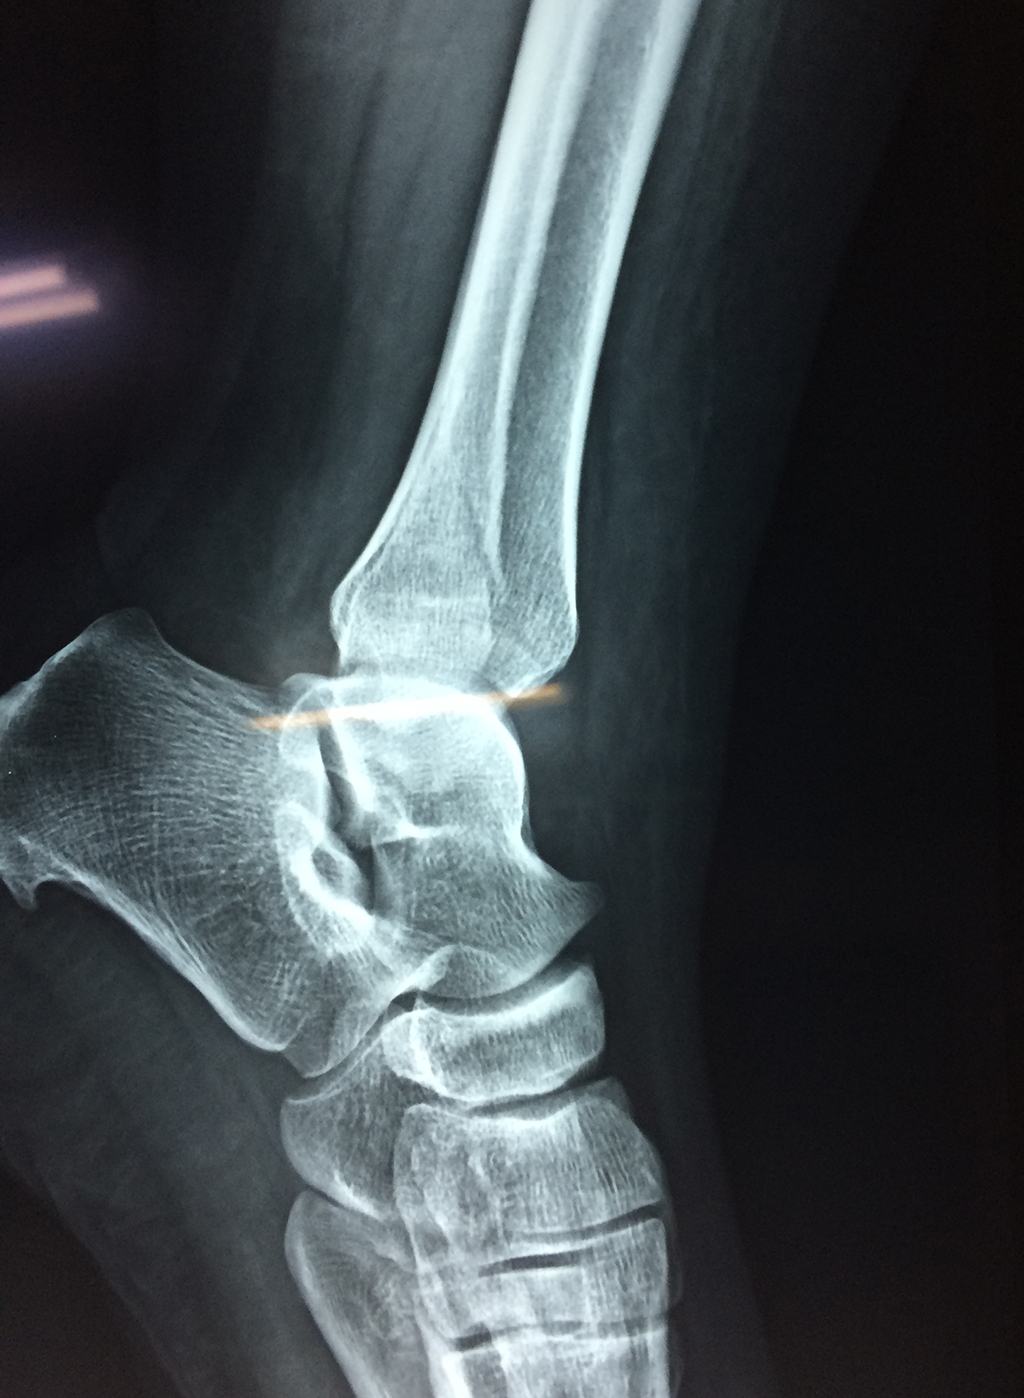

Algunas fracturas de tobillo pueden requerir cirugía si:

- Los extremos de los huesos están desalineados entre sí (desplazados).

- La fractura se extiende hasta la articulación del tobillo (fractura intra-articular).

- Los tendones o ligamentos (tejidos que sujetan los músculos y los huesos entre sí) están rotos.

- El médico cree que sus huesos probablemente no sanen apropiadamente sin cirugía.

- El médico considera que la cirugía puede permitirle una recuperación más rápida y confiable.